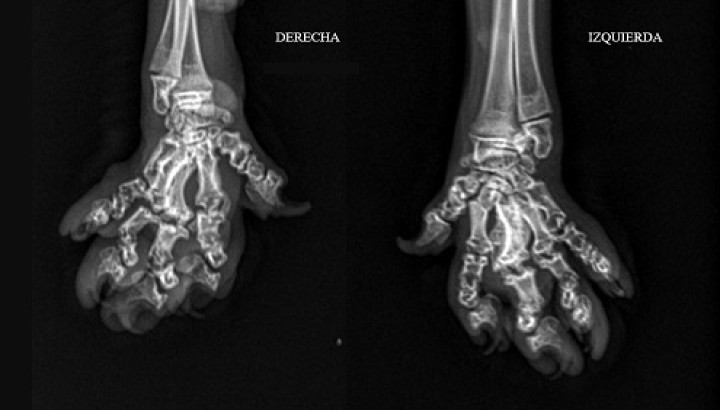

Ante la sospecha de una osteocondrodisplasia, está indicado realizar radiografías de la cola para valorar vértebras caudales, de los carpos, metacarpos y falanges, así como de los tarsos, metatarsos y falanges (Figs. 4 y 5). Estas mostraron acortamiento de vertebras coccígeas, así como de los huesos metacarpianos, metatarsianos y falanges, y deformación y degeneración articular a esos niveles.

<p>Proyección dorsopalmar de la parte distal de las extremidades anteriores (<em>manus</em>) del paciente donde se observan lesiones similares (aunque más leves) a nivel de carpos, metacarpos y falanges que los encontrados a nivel de tarsos, metatarsos y falanges en las extremidades posteriores.</p>

Proyección dorsopalmar de la parte distal de las extremidades anteriores (manus) del paciente donde se observan lesiones similares (aunque más leves) a nivel de carpos, metacarpos y falanges que los encontrados a nivel de tarsos, metatarsos y falanges en las extremidades posteriores.